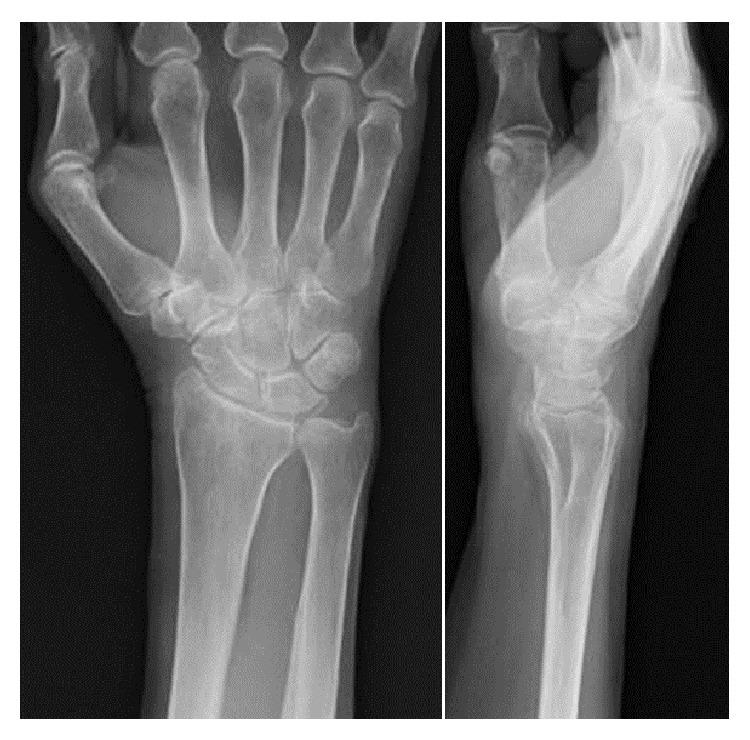

Introduction. Tumoral calcium pyrophosphate dihydrate (CPPD) crystal deposition disease (CPPDCD), also known as tophaceous calcium pyrophosphate deposition disease (CPDD), is a tumorlike lesion, and it should be distinguished from usual CPDD that causes severe joint inflammation and arthralgia. A case of tumoral CPPDCD of the wrist joint that required differentiation from synovial osteochondromatosis is described. Case Presentation. The patient was a 78-year-old woman with a 5-year history of nodular lesions at the right wrist that had gradually increased in size. An excisional biopsy and a histological examination of the excised nodular lesions by hematoxylin and eosin (H&E) staining were performed, demonstrating numerous polarizable, rhabdoid, and rectangular crystals, surrounded by fibroblasts, macrophages, and foreign body-type giant cells, consistent with tumoral CPPDCD. Conclusion. Tumoral CPPDCD, especially at the wrist joint, is rare, and, to the best of our knowledge, only 2 articles have been published. This case seems to need further follow-up for recurrence, because tumoral CPPDCD may recur after complete or incomplete surgical excision.